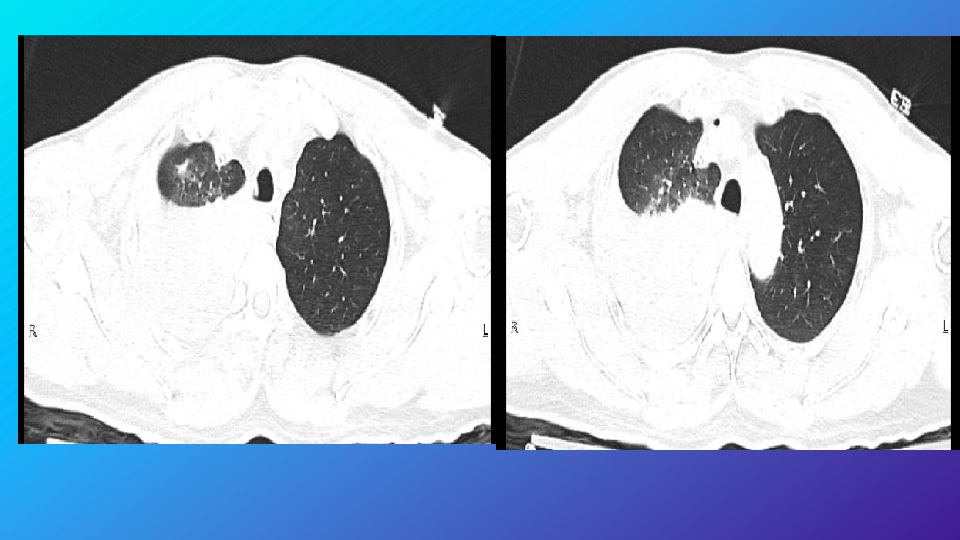

胸部外伤